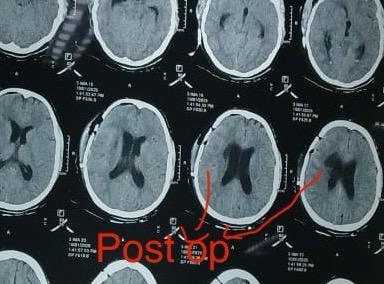

सफल सर्जरी के बाद तेज़ी से रिकवरी

करीब सात घंटे चली सर्जरी के बाद मरीज को अगले ही दिन वार्ड में शिफ्ट कर दिया गया। सभी ट्यूब और सपोर्ट सिस्टम हटाने के बाद तीसरे दिन वह अपने दैनिक कार्य करने लगी। पांचवें दिन उसे पूरी तरह स्वस्थ होकर डिस्चार्ज कर दिया गया। खास बात रही कि महिला रोगी का यह उपचार सरकार की योजना राज्य कर्मचारी बीमा निगम अन्तर्गत बिना पैसा खर्च हुए नि:शुल्क हो गया।